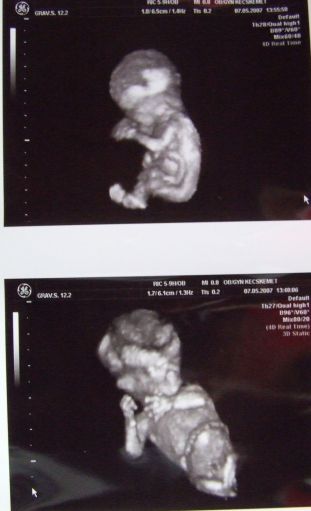

Képzeljétek, ma voltunk UH-n. Ez annyit dobott rajtam..... :D Olyan jó volt látni. Vert a kicsi szíve, és mozgott össze-vissza szegénykém. Zsófi sem szerette az uh-kat. Kaptunk fényképet is róla. :)

Tankónál voltam, minden rendben van, megvannak az újjai is, csontjai is szépek. A méretei alapján már 12 hetes + 5 napos vagyok. Nagyobb, mint egy 11 hetes + 1 napos baba (ez vagyok most elméletileg). De az a lényeg, minden jó. :) Tényleg olyan jó volt látni. :)

Lili, en erre szamoltam, igy nem esett tul rosszul. Aztan az uh mindenert karpotolt! :D Idonkent atkapcsolt 4d-re es kaptam ket kepet is! :D Minden rendben van!

A képek nagyon jók!!!!!A másodikon mintha a kukiját látnám :shock: (A férjem szerint az bármi lehet)Doki nem mondta a nemét?

én is néztem a második képet, hogy kuki-e az a valami, de aztán megállapodtam magammal, hogy az csak a köldökzsinór, ahogy csatlakozik... Na jól kielemeztük a kis tejót :D

Hihetetlen jól látszik mindene a képen,nem is láttam még 2D-ben ennyire élethű képet!Nagyon édi,ahogy elképzelem,hogy milyen pindurka még,s ilyen kisemberke már :D

Mi is voltunk kedden orvosnál.Olyan édes volt a babó,mikor átkapcsolt a 4d-re épp vigyorgott egy nagyot.És megerősítették,hogy kislány.Ja és Ő is tiszta apja,mint Lilla. :D